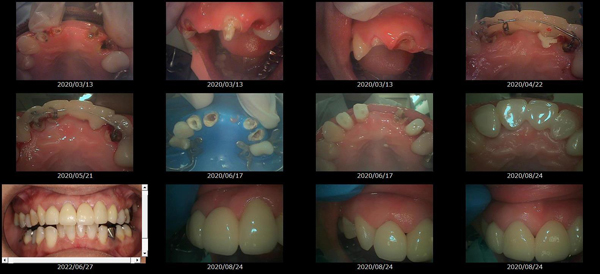

歯の形、歯並び、歯肉ラインが整う美しい口元

大掛かりな歯ぐきの手術や装置を使った矯正治療を行わずに、たった2回で歯並びをきれいに整えることができます。

術前

-

術後

BTAテクニック® とは

従来のセラミックで治すオールセラミックという被せ物や、セラミックを張り付けるラミネートべニアという方法に、歯科医師と歯科技工士の双方の手法と技法を癒合させることで、可能とした 歯ぐきのラインを2回の来院で、綺麗に仕上げ、歯の見た目も審美的に出来るテクニックのことである。

BTAテクニック® 以外の一般的な治療で歯ぐきのラインを整えるには、歯ぐきを切り、骨を削る手術をすれば可能ですが、歯ぐきの治りに数か月の期間が必要です。もしくは、矯正治療によって、歯並びを改善する方法、もしくは神経を抜いて、被せ物をするしかありません。

BTAテクニック® を用いると、歯ぐきや骨への手術が必要ない為に、治療期間が短縮でき、2回の来院で完了できるメリットがある。 また、この方法を用いることで、年々歯ぐきが下がって見た目が悪くなるということが起きにくくなる。歯周ポケットと言われる溝が浅くなり、歯ブラシが容易になる。などの利点が挙げられる特殊なテクニックである。

また、救歯BTAセラミックは、BTAテクニック®が持つ成功する理由(*)から、深い位置まで虫歯が進行してしまって歯を抜かないとならない歯に応用する事で、抜かずに治療することが出来る場合がある。

症例によっては、BTAテクニック® , 救歯セラミックが適応出来ない場合があります。 また、この方法を用いることで必ず歯が残せるという治療方法ではありません。

価格

> 1歯 165,000円